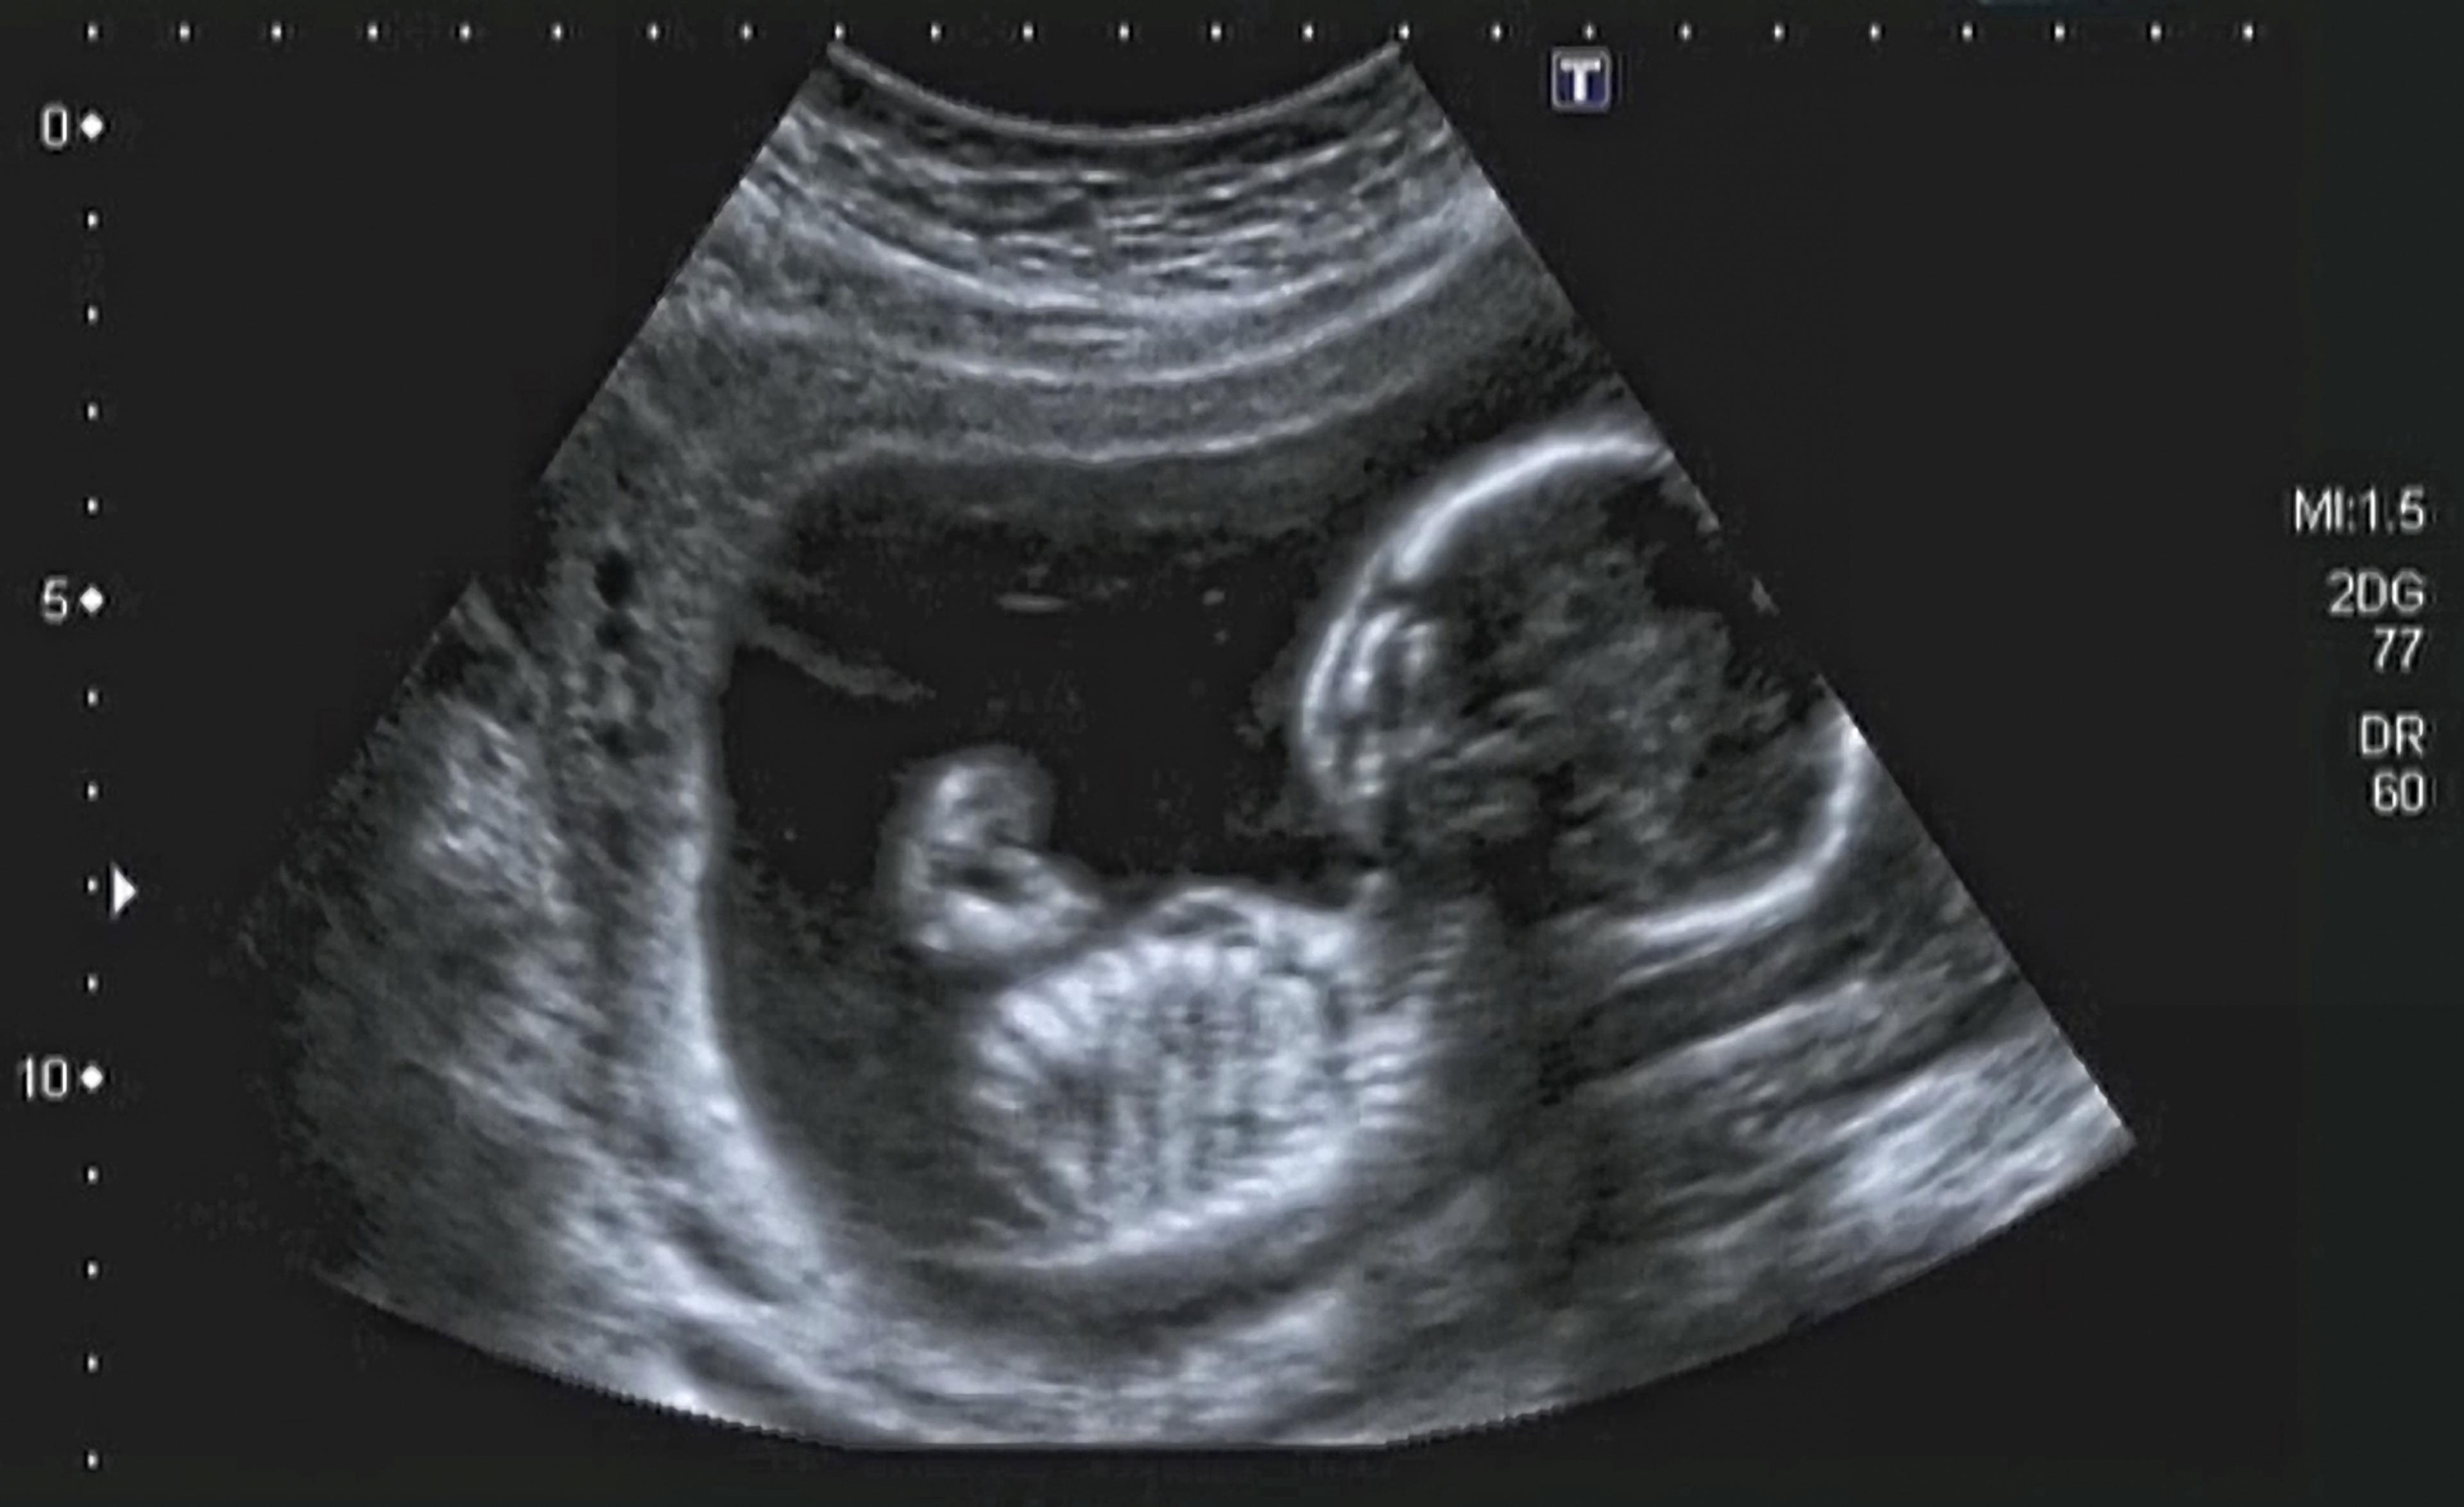

Gravida erbjuds fosterscreening, men det är frivilligt att delta i den. Screeningundersökningarna är gratis för gravida kvinnor. Efter att ha fått tillräcklig information avgör den gravida själv om hon vill delta i undersökningarna. Det går att ändra sig om beslutet när som helst under screeningen, utan att det påverkar graviditetens uppföljning eller behandling. Fosterscreeningarna utgörs av ultraljudsundersökningar, analys av markörer i mammans blodprov samt en kombination av dessa. Avvikande screeningresultat innebär inte sjukdom hos fostret, utan indikerar en förhöjd risk för fosteravvikelse. Ett normalt screeningresultat garanterar inte att barnet är friskt.